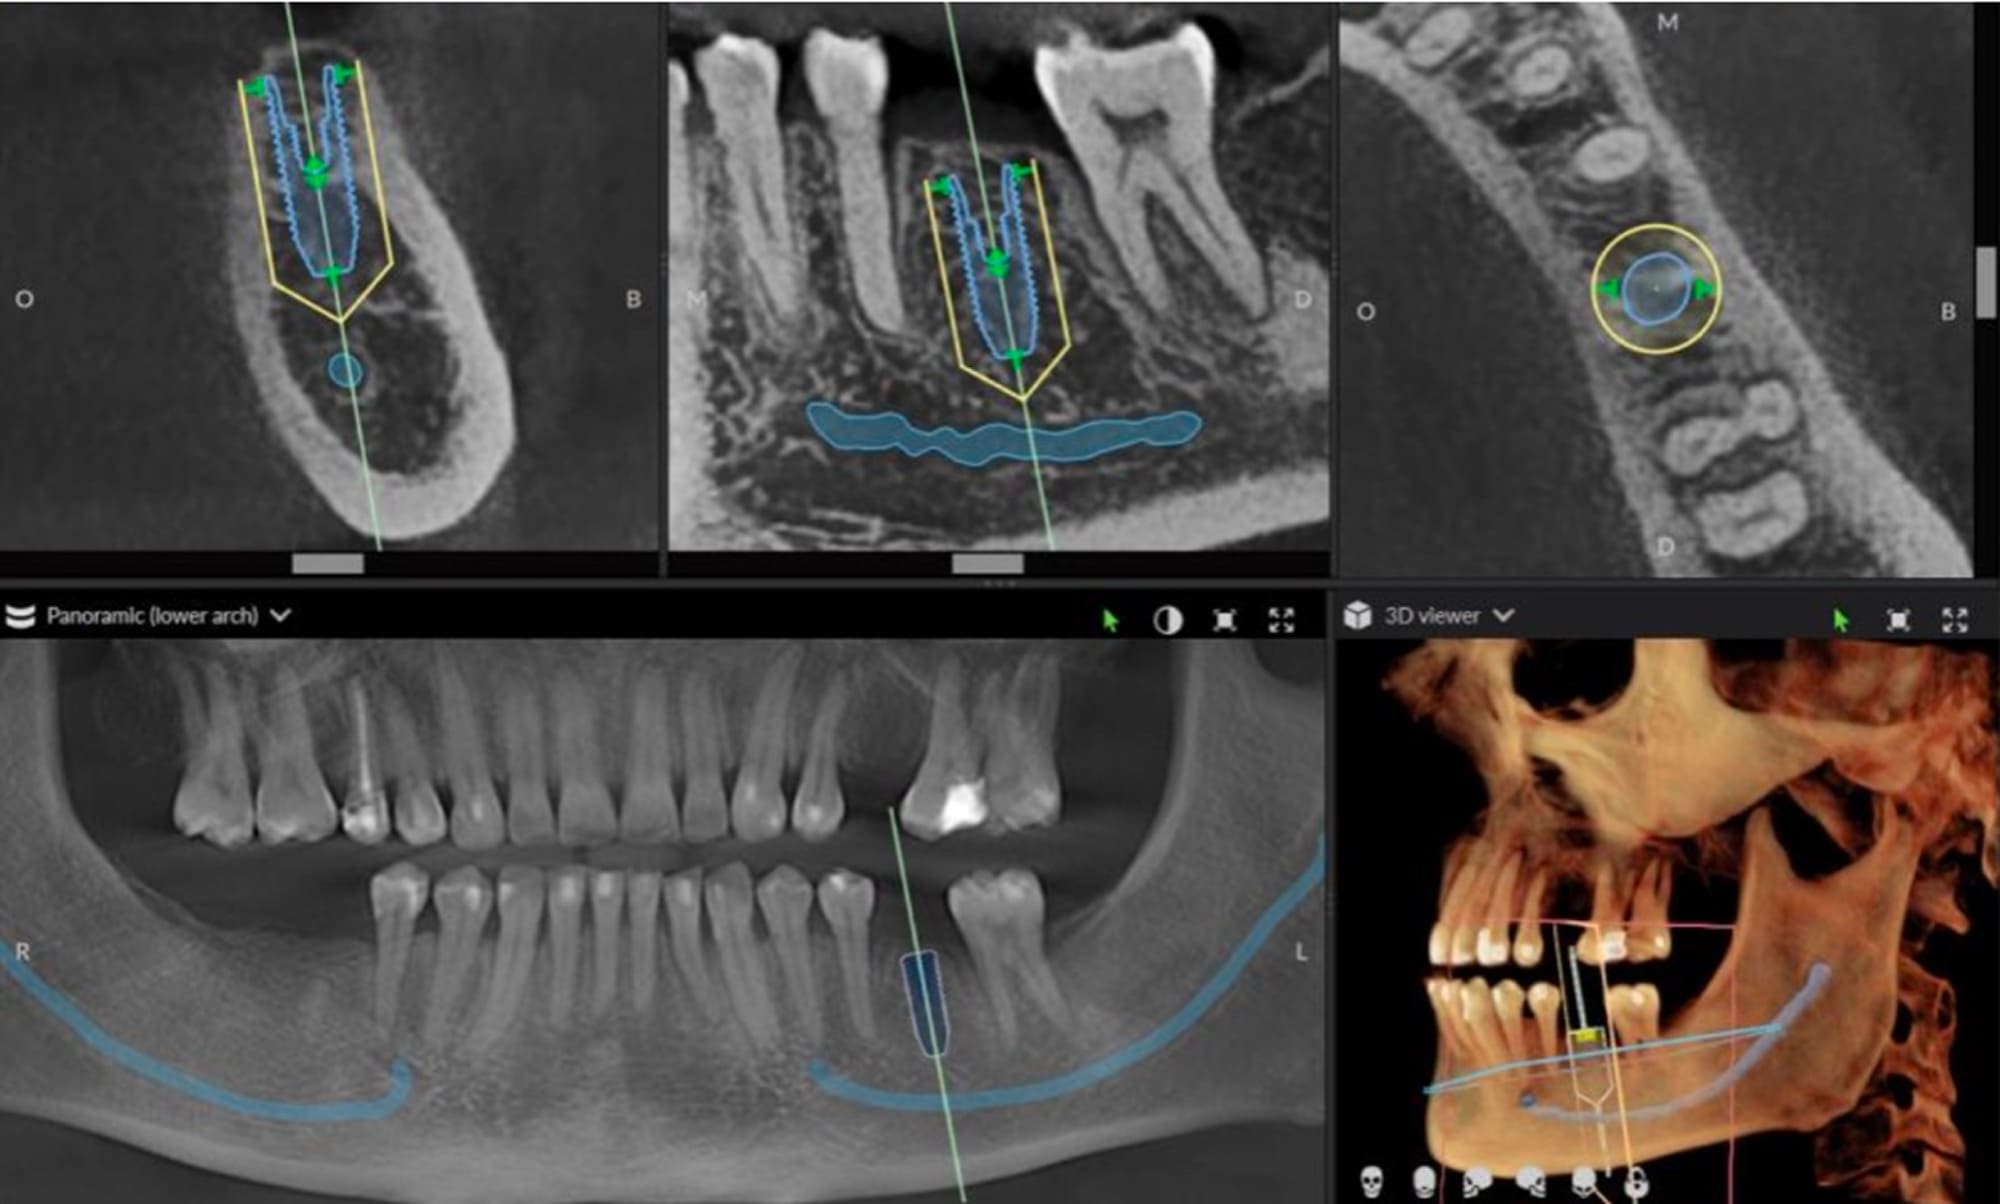

インプラントは、顎の骨に直接固定されるため、治療には一定の外科処置が必要です。当院では、インプラント手術の際にサージカルガイドを使用しており、事前にCT画像をもとに精密なシミュレーションを行ったうえで、インプラントを理想的な位置・角度に埋入できるようにしています。これにより、骨の厚みや神経の位置を的確に把握し、安全かつ高い精度で治療を進めることが可能です。

当院では、術前にCTや口腔内スキャンを用いた精密な診査・診断を行い、患者さん一人ひとりに最も適した術式をご提案いたします。どちらの術式でも、痛みや腫れを最小限に抑えるよう配慮しながら、安全性と快適性を重視した治療を行っています。